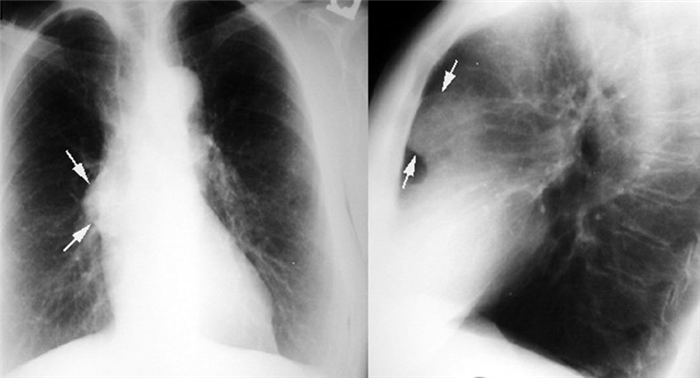

Большинство тимом можно обнаружить с помощью обычной рентгенографии. Опухоль выглядит как тень с ровными краями в верхней половине грудной клетки. Она частично перекрывает тень от сердца, находится преимущественно справа или слева.

На рентгенограмме в медиальных отделах верхушечной, верхней и средней зоны правого легкого видна интенсивная полуовальная тень, сливающаяся своим медиальным контуром с тенью средостения. На фоне тени имеется плотное включение неправильной формы. В боковой проекции образование это располагается в передневерхнем и задневерхнем отделах средостения.